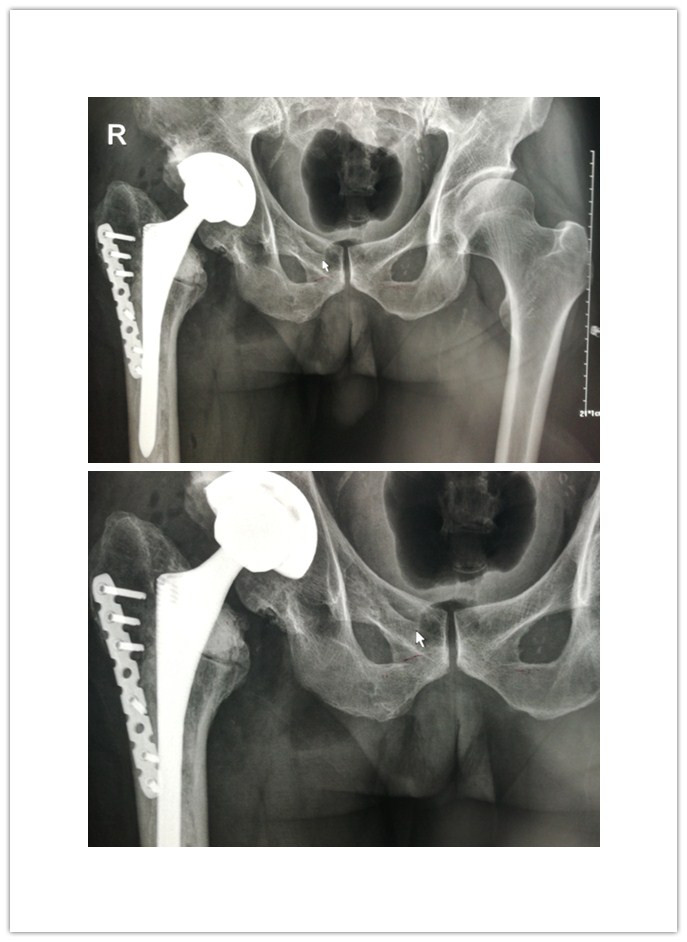

患者王先生,63岁,因半月前不慎摔伤右下肢,在家休息后疼痛加重,遂来我院就诊。骨一科刘波主任接诊后,详细询问其过往病史,得知患者29年前因右侧股骨颈骨折,在济南某医院行右侧人工股骨头置换术,术后右下肢行走良好;但8年前,右髋部疼痛复发、跛行愈加厉害;加之此次摔伤,致使病情加重。经X线检查示:右侧股骨头置换假体下沉,右腓骨远端骨折;且查体后发现其右下肢较左下肢短约5cm。刘主任考虑到王先生年岁已高,且体内假体已有29年,早已超出使用年限,遂决定为其行右侧人工髋关节翻修术。

手术于腰硬联合麻醉下进行,刘主任联合手术医师另行切口,采用钢丝捆绑的方法取出原来关节假体,并重新磋磨髓腔、髋臼,安放新的髋臼假体;随后用骨水泥固定股骨柄假体,并在股骨大转子外侧壁的劈裂骨槽处用接骨板复位坚实固定。术中克服种种不利因素,用时近4个小时,顺利完成右侧髋关节翻修。

术后,刘主任及时为患者量身制定了功能康复锻炼方案,在骨一科医护人员的精心指导下,王先生右下肢功能逐渐恢复。X线检查示:右髋部假体位置良好,力线良好;经术后测量右下肢较左下肢长度相差1cm,基本恢复双下肢等长。术后14天,王先生已能够拄拐下地行走,并顺利拆线出院。该手术的成功标志着我院骨一科在我县骨科临床技术领域获得质的突破。